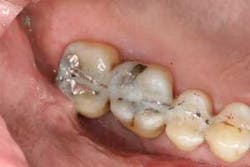

Figures 2a and 2b: Initial presentation in 2011 of the upper right and left molar area, showing advanced bone loss with furcation involvement on the molars.

At presentation, Martin was in his fifties with a medical history significant for controlled hypertension with no known food or drug allergies. He had been lackadaisical with his dental care in the past because of his busy schedule, but he was motivated to get his hygiene and treatment under control. He denied a history of smoking/alcohol/drug use. Based on his full-mouth series (figure 1) and clinical presentation, Martin had generalized, moderate bone loss with localized, severe bone loss in the posterior maxillary right and left quadrants (figures 2a and 2b) as well as the mandibular anterior incisor area (figure 3).